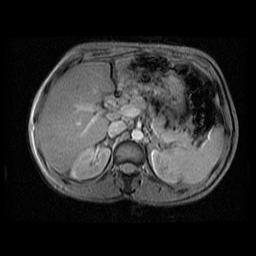

a) Si la mutation est présente à l’état homozygote (C282Y +/+), l’hémochromatosie peut être affirmée. La stratégie repose alors sur l’évaluation de l’intensité de la surchage hépatique en fer. Celle-ci est obtenue par l’utilisation combiné du taux de férritinémie et des données de l’IRM hépatique [5]. Les valeurs seuils actuellement proposées par les équipes sont un taux de 1000 à 1500 ug/l pour la férritinémie et/ou une C.H.F par IRM déduite du degré de l’hyposignal en T2 de l’ordre de 400 à 500 umol/g.

IRM hépatique sur hémochromatose

Copyright - Yves Gandon - Imagerie Médicale -Rennes.

Si ces paramétres orientent vers une probabilité trés forte d’observer une cirrhose une ponction biopsique hépatique (PBH) doit être réalisée. Elle est alors justifié comme élément de pronostic pour d’une part apprécier l’existence et le degré de fibrose et d’autre part rechercher la présence d’un carcinome hépatocellulaire ou de nodules hépatiques dépourvus de fer qui interviennent dans la genése de ce dernier.